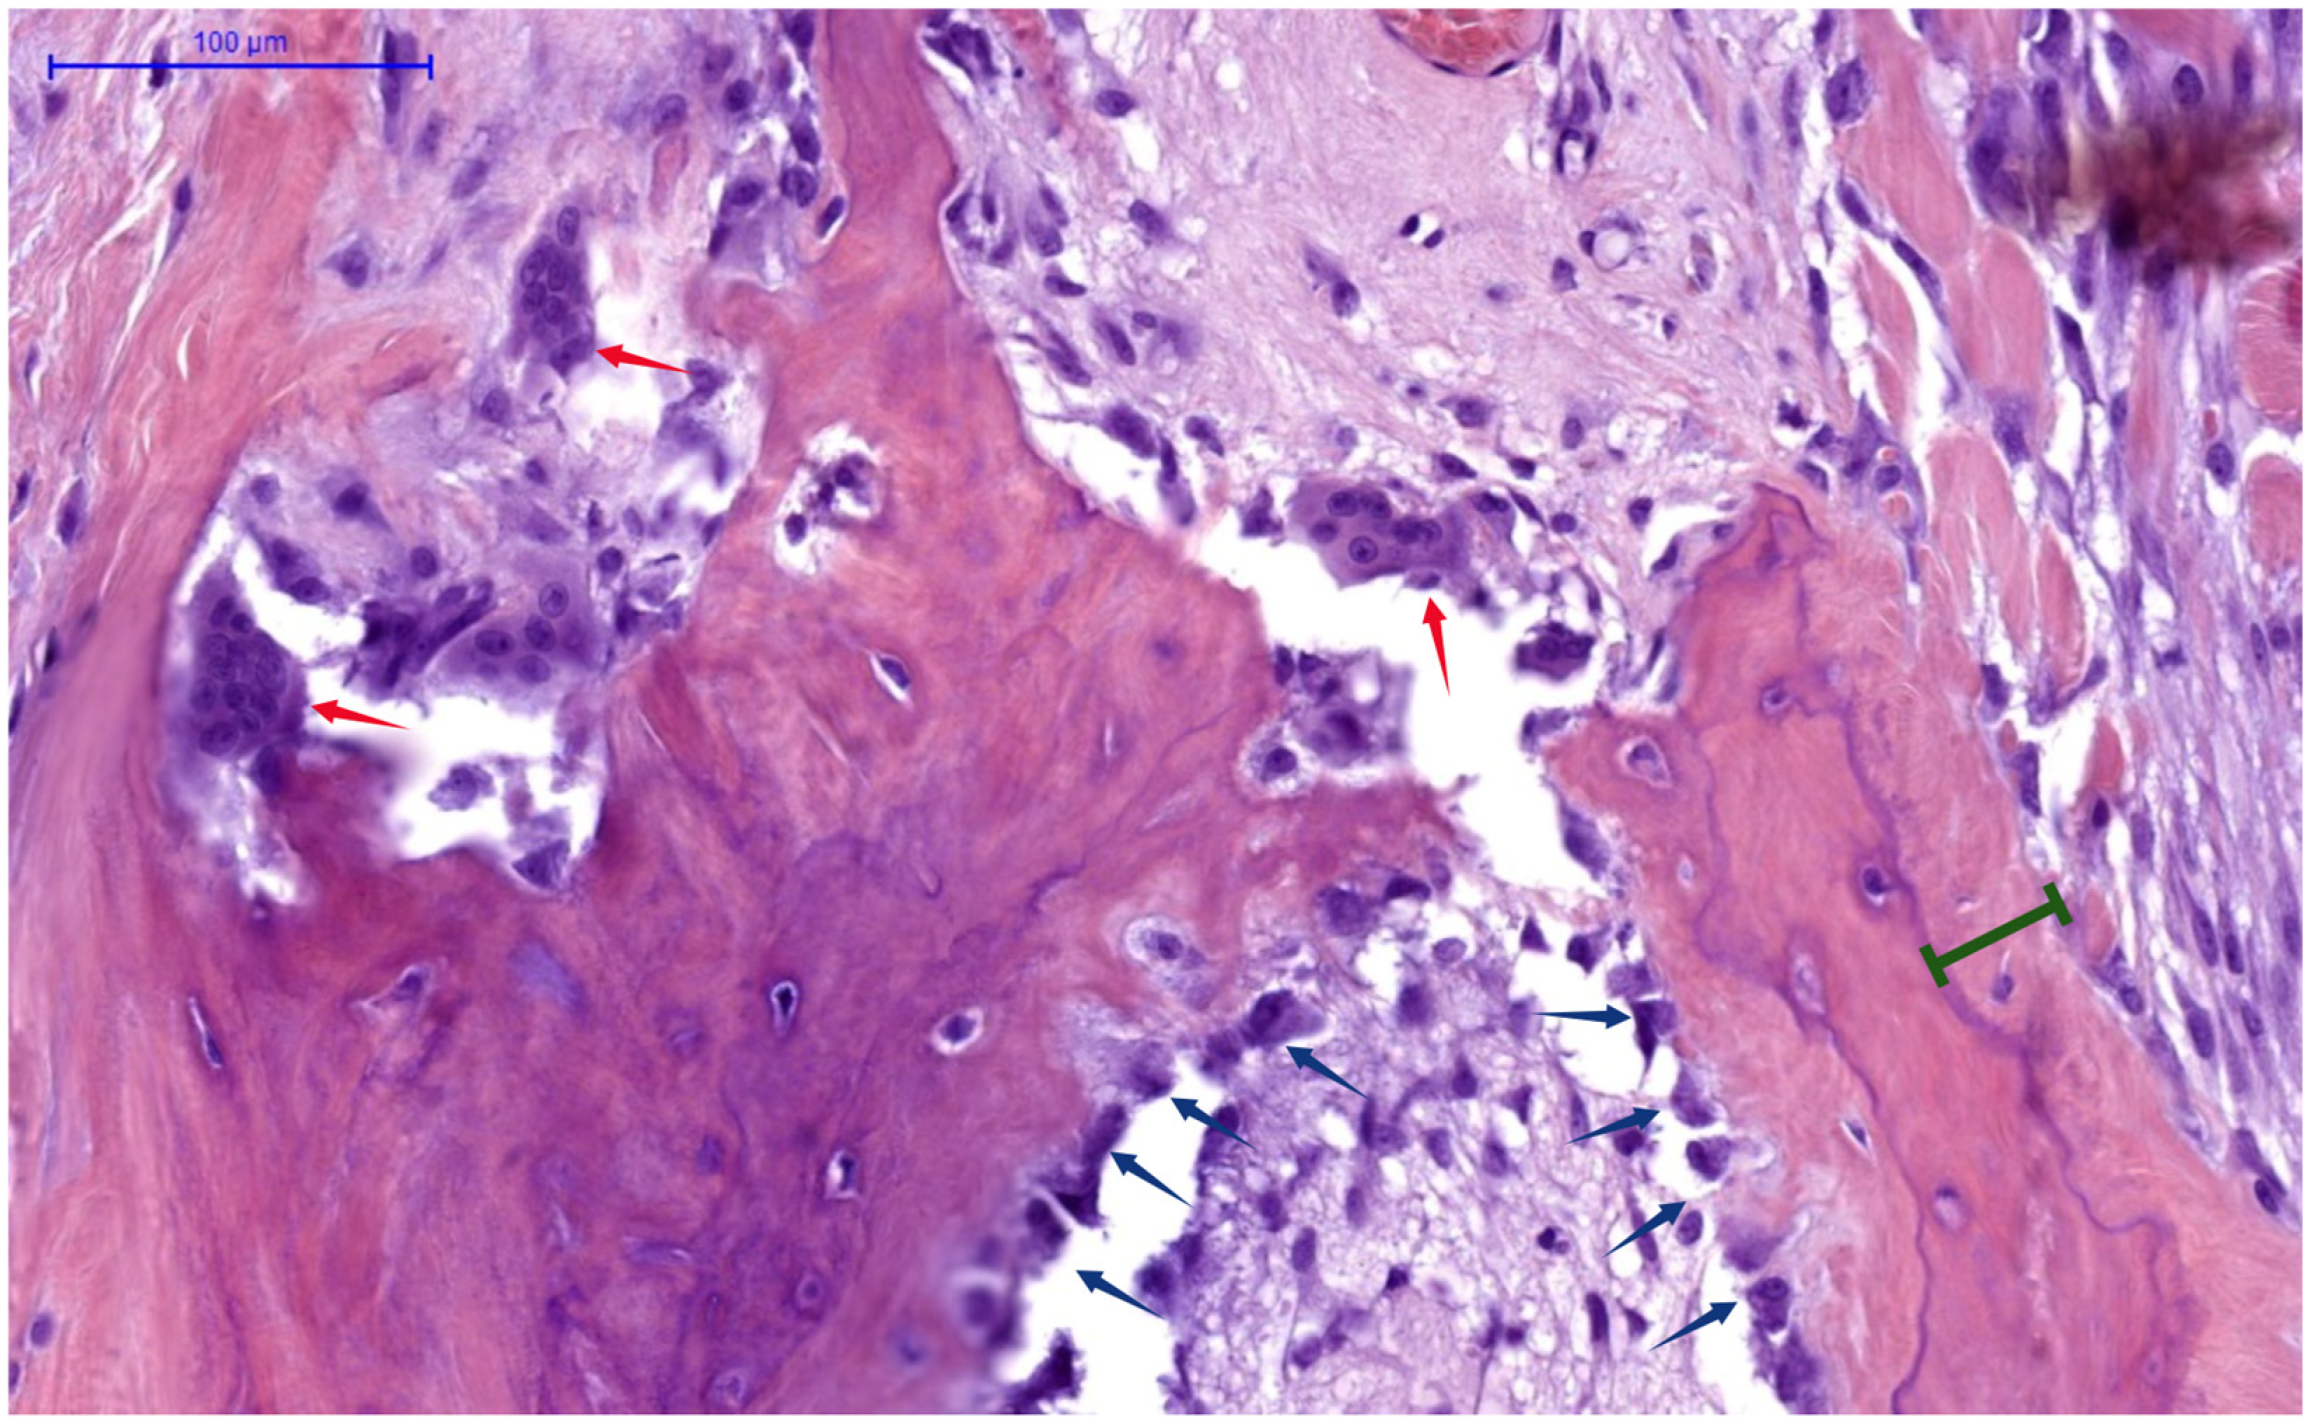

- Skeletal Burden of Disease: Patients with overt skeletal manifestations of SHPT (e.g., osteitis fibrosa cystica, subperiosteal bone resorption on X-ray, or brown tumors) inherently have very high bone turnover and large calcium deficits, predisposing them to severe HBS. In contrast, those with mixed uremic osteodystrophy or adynamic bone (often seen in longstanding diabetes or with calcimimetic overuse) have lower turnover and thus lower HBS risk. A bone biopsy (though rarely done pre-PTX) showing high turnover and abundant osteoid would strongly predict HBS. Similarly, very low pre-op bone mineral density could indicate high turnover bone loss.